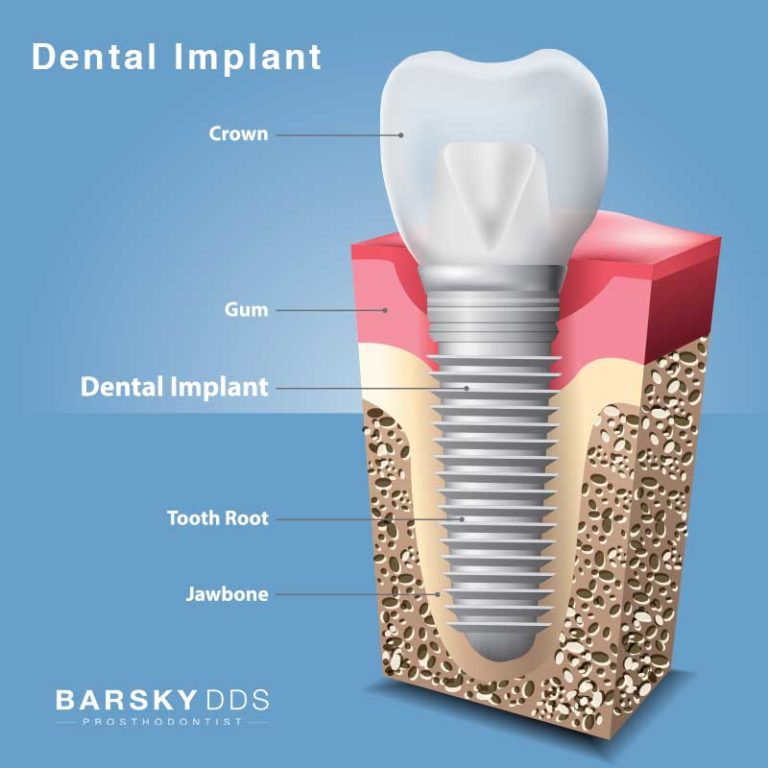

The Anatomy of The Dental Implant | Knoxville TN Dentist

What is a Dental Implant? | DDi

Dental Implant, Single Tooth

How dental implants work – Dental News Network

How do dental implants work? ⋆ Dental House

Dental Implants Portland OR | What Are Dental Implants